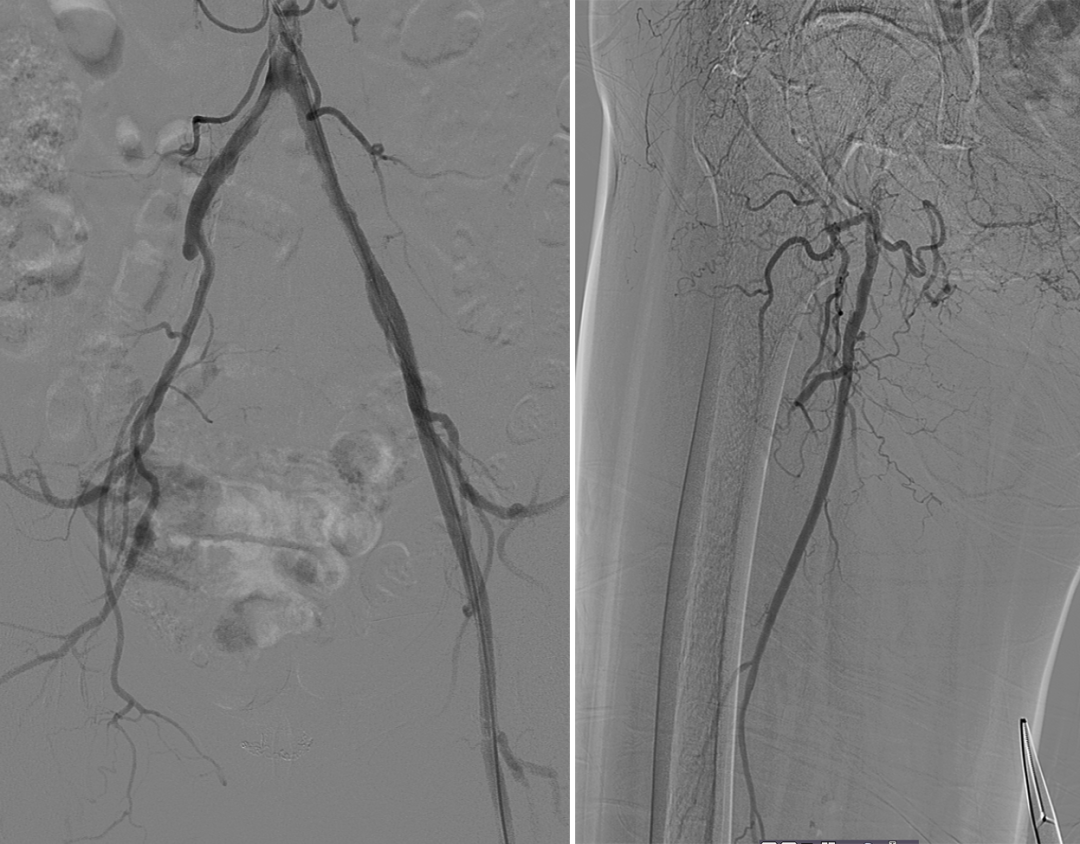

造影显示右侧髂外动脉、股动脉血栓栓塞。

Roterax吸栓后血流较前通畅,球囊扩张后局部夹层伴狭窄。

在狭窄端植入6mm*80mm Smartcontrol 支架1枚,造影显示血流通畅,予Exoseal 封堵穿刺点。

第二次术中造影资料

顺行穿刺无法开通,行左侧腘动脉逆行穿刺,超选进入顺行导管。

球囊扩张全程血管,显示支架内有陈旧性血栓,予6F导管吸栓,最后造影显示血流较前通畅,部分附壁血栓继续抗凝治疗,定期随诊。予Exoseal封堵穿刺点。